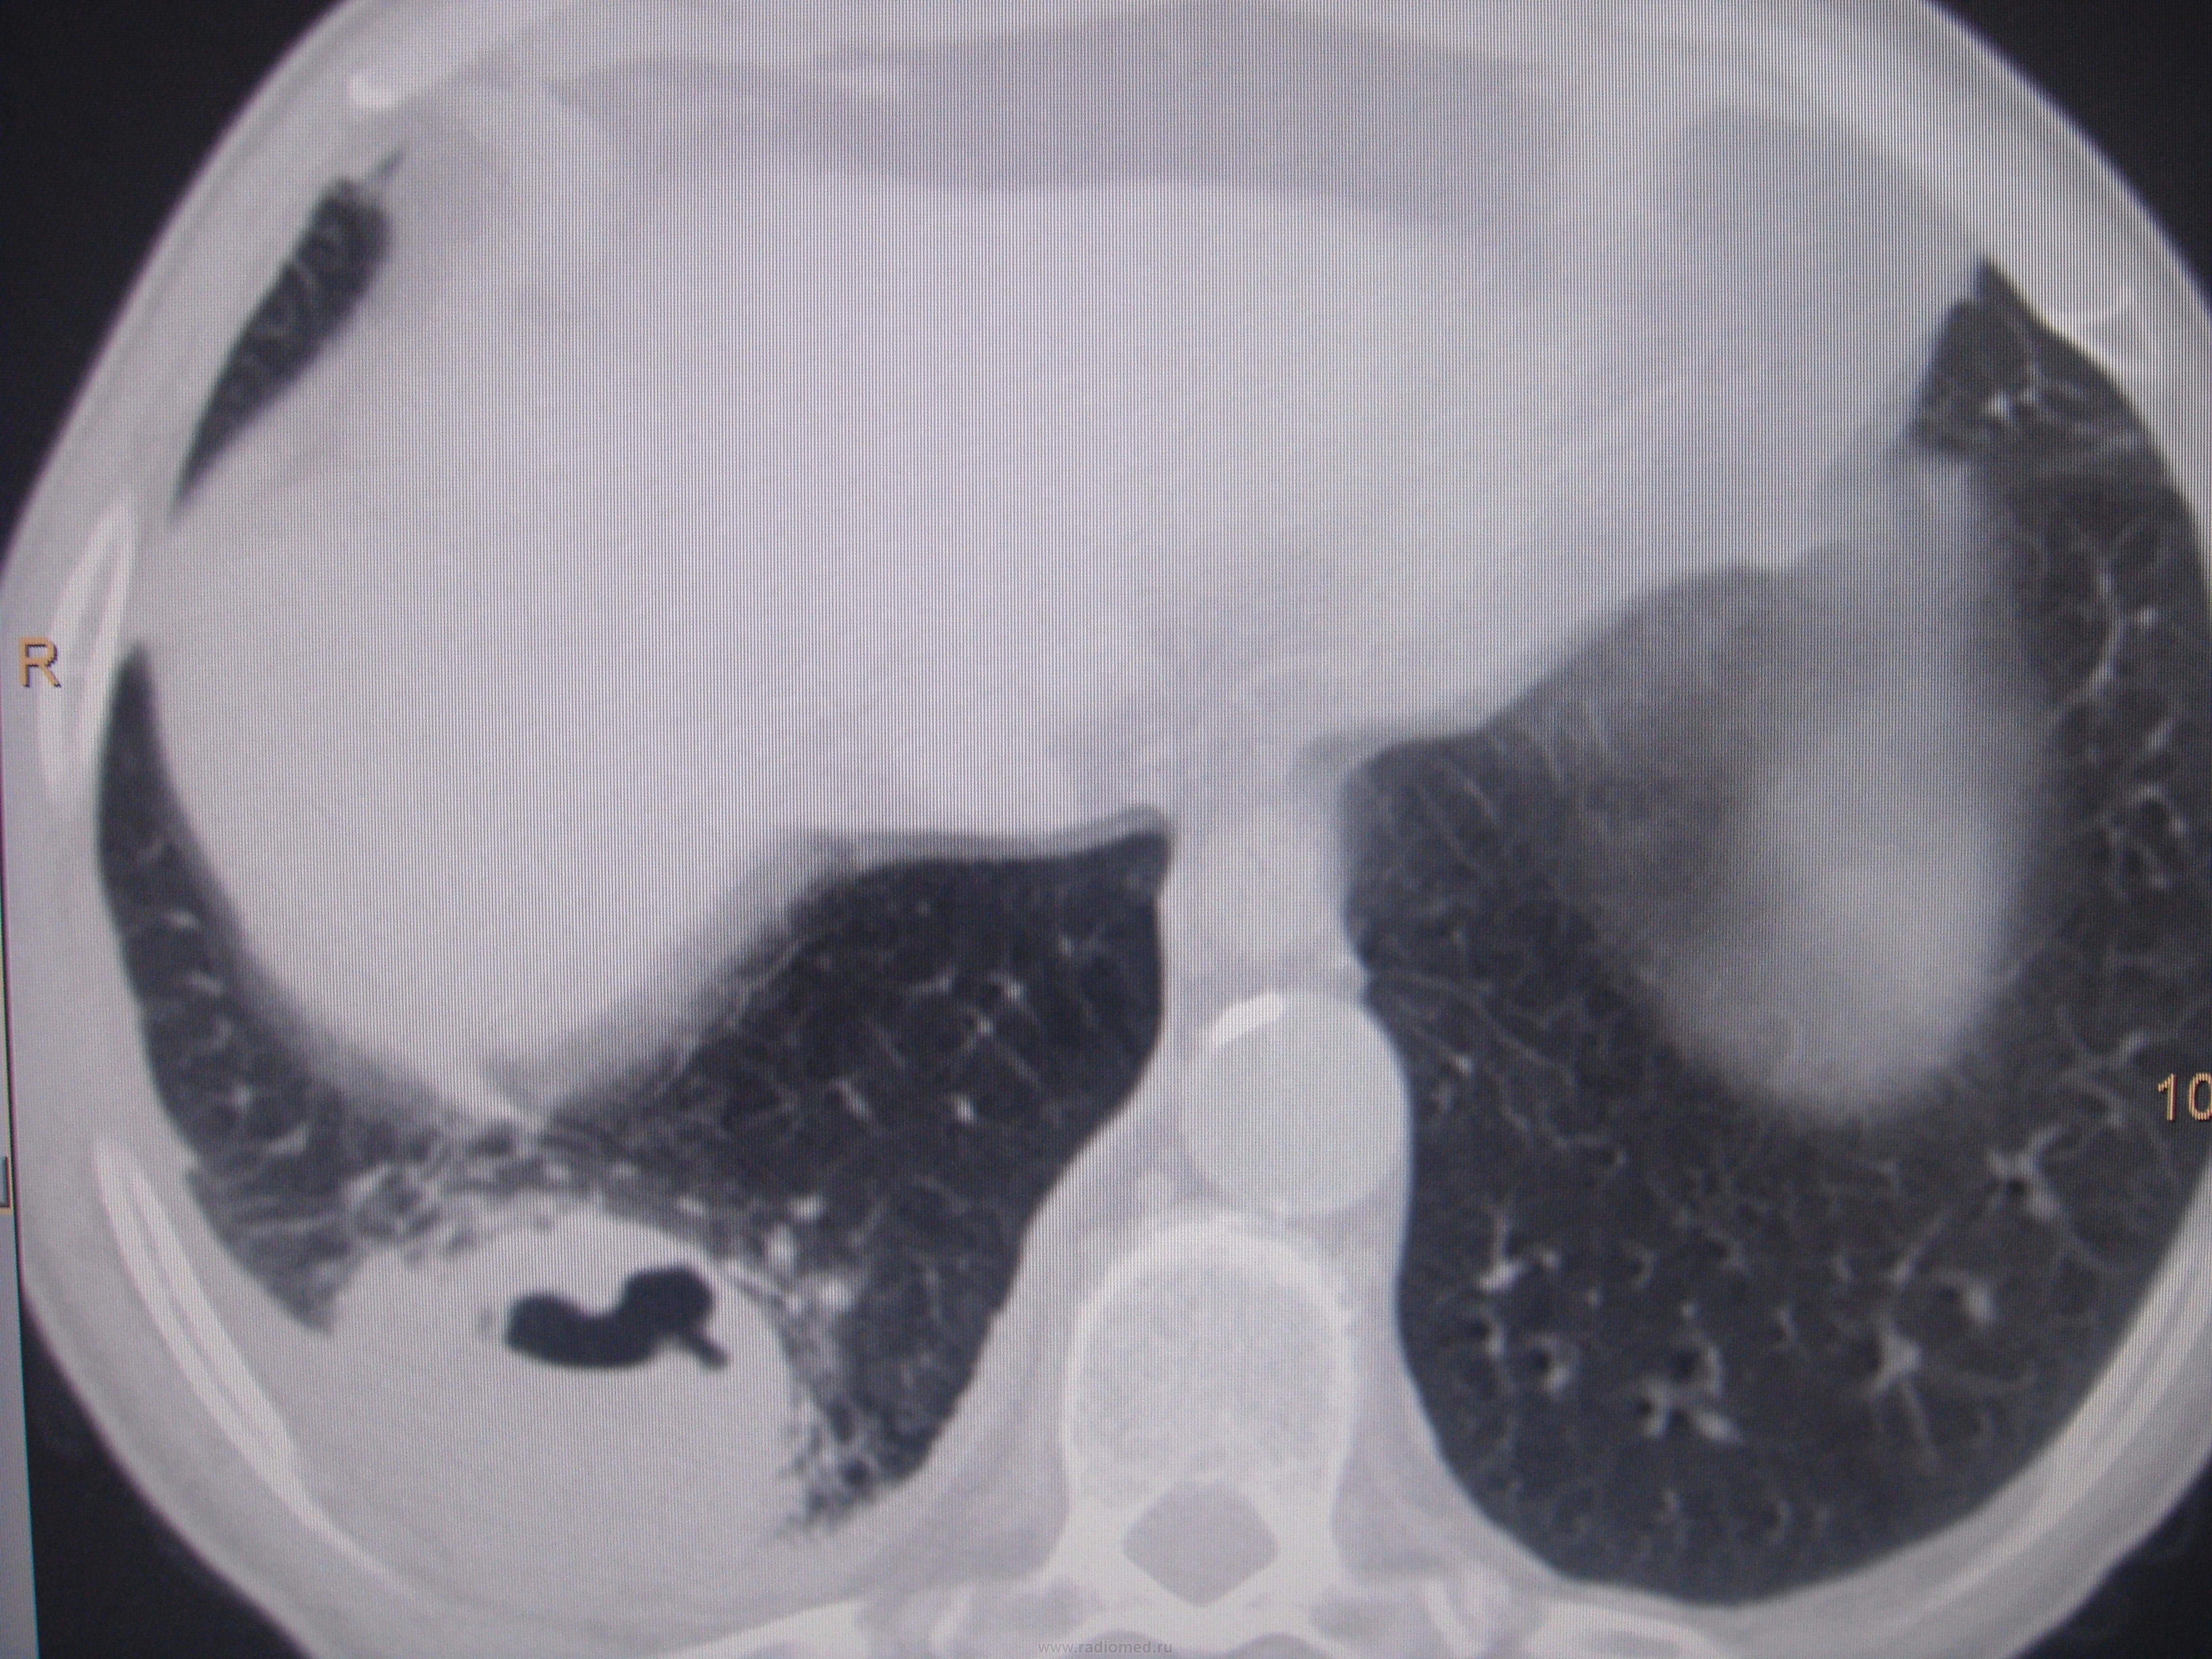

Больной лечился у невролога, провели проф ФГ- выявили деструктивную пневмонию, пролечилили, на Р контроле- ухудшение, клиники абсцесса не было, была боль в гр клетке спереди справа. Из анамнеза- лечился оперативно 6-7 лет назад по поводу рака верхней губы, в ООД не наблюдался последние годы. Данные за туб этиологию сомнительны, как мне кажется, очагов отсева по слоям не вижу,  хотя мож не так смотрю. Ваше мнение коллеги, абсцесс это или нет?

По опыту хочу сказать, что в настоящее время классической клиники абсцесса можете и не увидеть. Очень она изменилась. В данном случае контроль  должен помочь. В связи с тем, что стенки имеют разную толщину и вокруг почти нет изменений, больше склоняюсь к полостной форме рака.